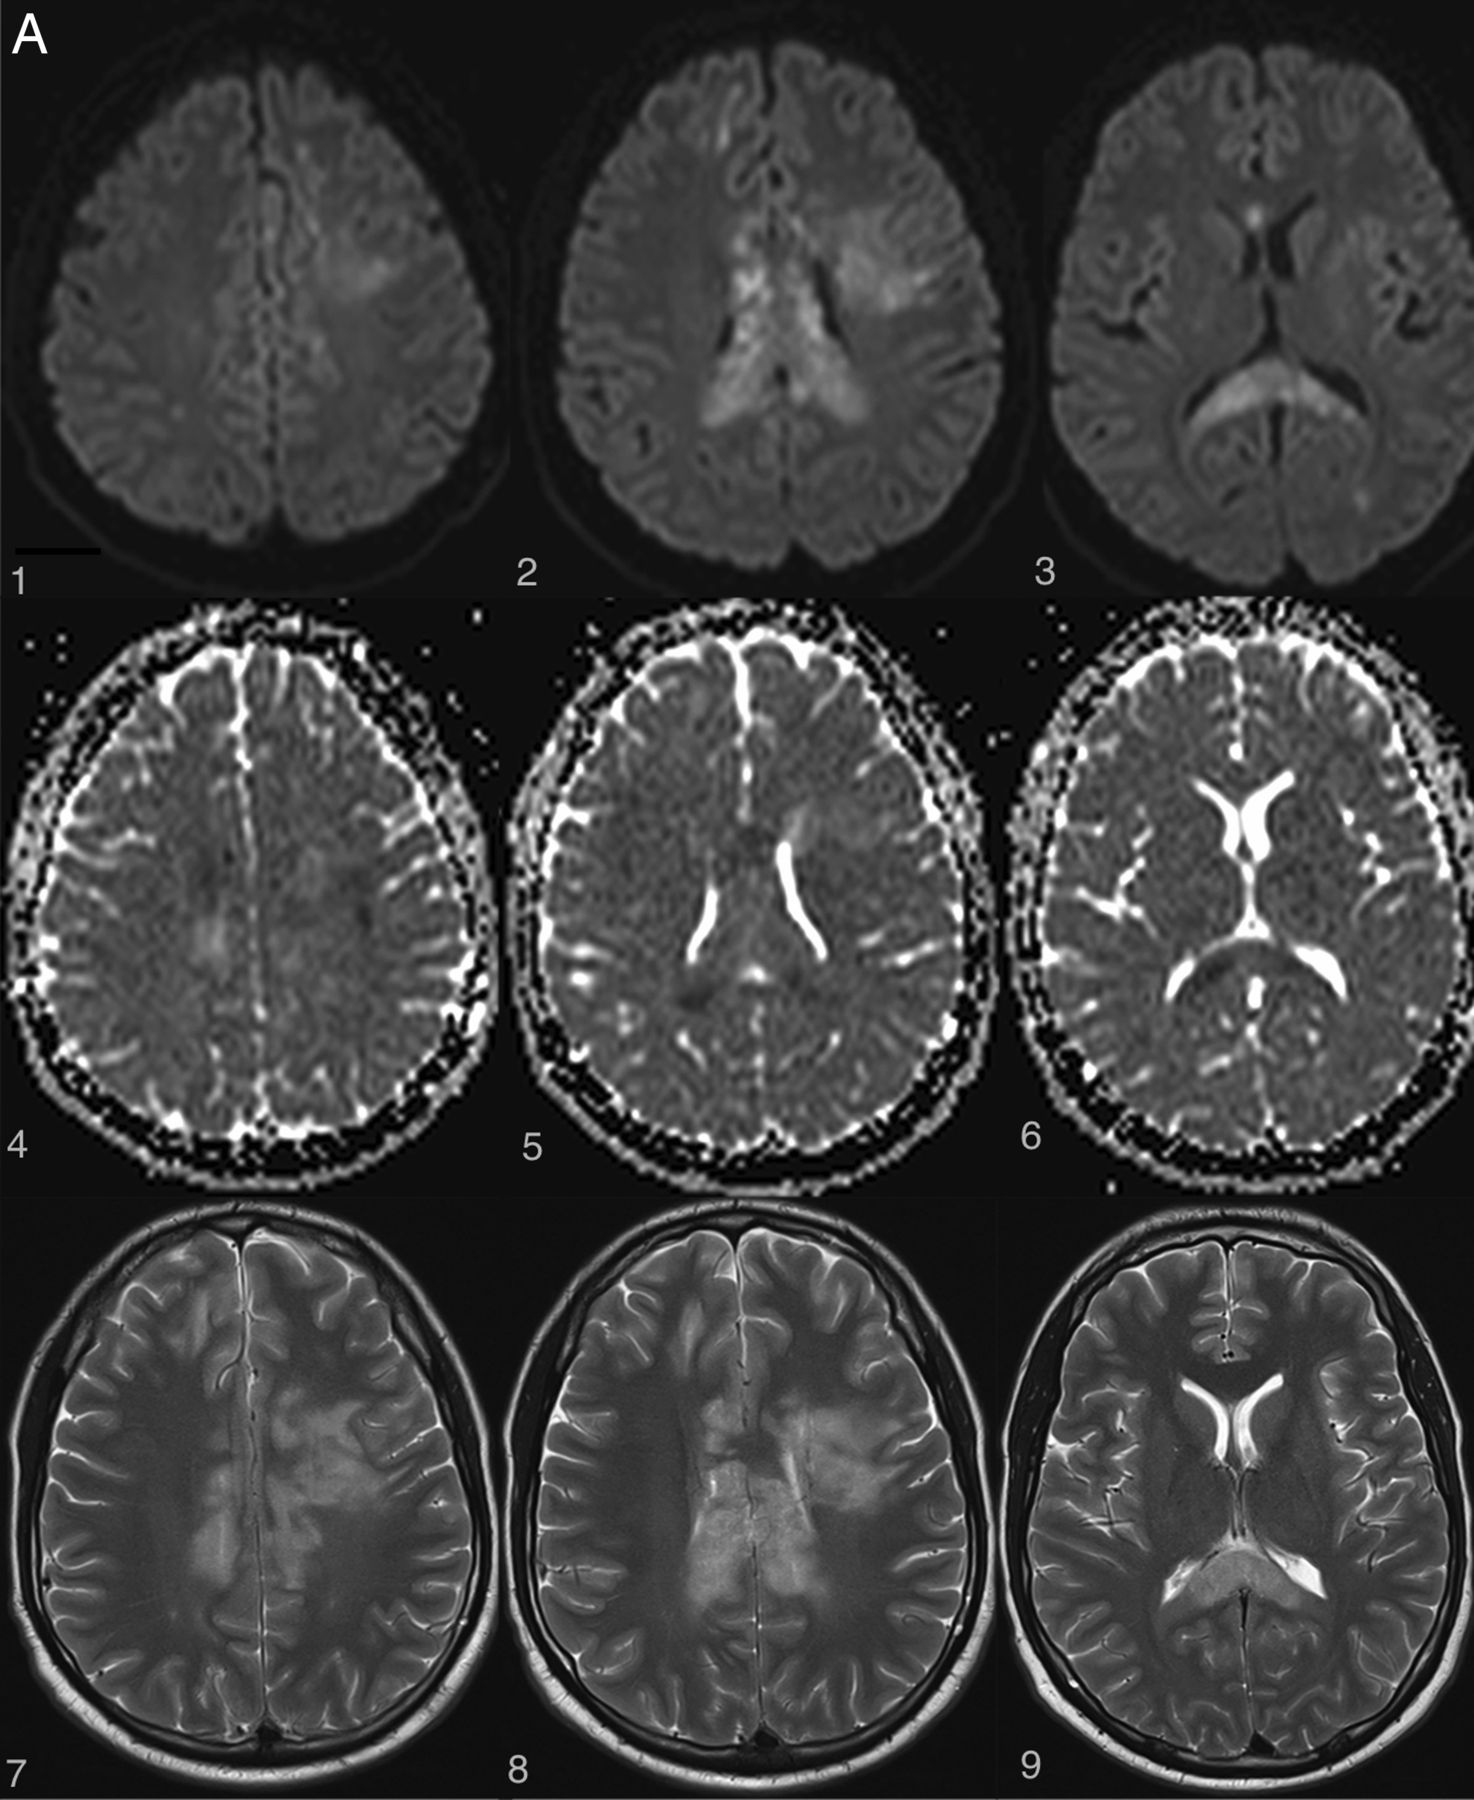

Examples of irreversible brain and spinal cord lesions due to decompression sickness (A, B, and C are taken from the same patient). A, On DWI (1, 2, 3, 4, 5, 6), the areas of restricted diffusion correspond to lesions of the corpus callosum and frontal white matter on both sides. They appear as high signal on T2WI (7, 8, 9). B, Sagittal (1 and 2, white arrows) and axial (3 and 4, white arrows) T2WI shows a cervicothoracic (C7–T1) lesion appearing as high signal without contrast enhancement on T1WI (2). C, On follow-up 1 month later, the lesions described in A and B are still present on these brain (1, 2, 3, 4) and spine (5, 6) images. Note the enhancement of the corpus callosum (3 and 4). Lesions of the right frontal deep white matter and corpus callosum have healed and now appear as “little cavities.” Similar features are usually seen in ischemic or necrotic lesions of the central nervous system.

The exact mechanism through which nitrogen bubbles cause brain and spine damage is still highly debated, and there are currently 3 theories supporting 3 different pathophysiologic mechanisms: arterial occlusion, venous infarction, and in situ nitrogen toxicity. The following support the arterial occlusion theory: 1) the predominance of cerebral lesions in arterial gas embolisms with usually a clinical and radiologic stroke-like presentation (restricted diffusion appearing as hyperintensity on DWI with low values on the ADC map, high signal on T2WI, and usually no contrast enhancement) (Fig 3A).7,21,22 2) The finding that nitrogen bubbles can interrupt arterial blood supply to the brain and spine either by direct obstruction of small capillaries or by activation of pathologic clotting at the blood-bubble interface.23⇓⇓–26 This effect on clotting is increased in case of low hematocrit, explaining the higher risk of severe cardiopulmonary and neurologic decompression sickness in dehydrated divers.27⇓⇓–30 3) The higher prevalence of a patent foramen ovale in patients experiencing decompression illness31⇓⇓⇓⇓⇓⇓⇓–39 could favor paradoxic embolization of either nitrogen bubbles or pathologically formed thrombi with subsequent ischemic infarcts in the brain40 or spine, where the collateral circulation network is less robust.41 4) The presence of extensive gray matter lesions in some neurologic decompression sickness cases—gray matter lesions being typically seen in arterial infarction processes.11,18,42 5) Hypoperfused areas compatible with embolic cerebral arterial occlusion are observed in some patients with decompression illness when using SPECT with hexamethylpropyleneamine oxime (HMPAO) marked with a metastable nuclear isomer of the radioisotope technetium Tc99m (the product is sometimes referred to as exametazime).43,44

On the other hand, various radiologic and histopathologic findings have been published to support the venous infarction theory. First, the more frequent occurrence of lateral and posterior column white matter lesions compared with gray matter lesions in spinal cord decompression sickness is more likely a consequence of an obstruction of the slow-flowing epidural venous bed by nitrogen bubbles, which leads to vasogenic edema (Figs 1 and 2).5,8 In some cases, there may be additional venous infarction (Fig 3B, -C). Similar lesions have been provoked experimentally in dogs.9 Second, several histopathologic studies have demonstrated venous obstruction and white matter congestion.45,46 Third, vasogenic edema, appearing as high signal on both DWI and ADC maps, was observed by Vollmann et al in 201147 in a case of spinal cord decompression sickness, also suggesting a venous rather than arterial pathologic process.

Authors of MR imaging studies of decompression illness frequently report that the different clinicoradiologic patterns mentioned above overlap in the same patient, thereby suggesting that no single unifying pathophysiologic mechanism could completely explain this complex condition.14,16,47 Some have argued that there is a greater participation of arterial occlusion in brain lesions because they are more frequently described in cases of arterial gas embolism, while venous occlusion may play a greater role in spine lesions and may even be favored by local mechanical cord compression.11,15 Whatever the preponderant mechanism involved, the treatment is urgent hyperbaric therapy to allow nitrogen to dissolve and be expelled via the lungs.